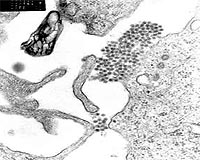

An HIV-like virus that infects monkeys is thousands of years older than previously thought and its slow evolution could have disturbing implications for humans, according to a new study.

Scientists said the simian immunodeficiency virus (SIV) -- the ancestor to the human immunodeficiency virus (HIV) that causes AIDS -- is probably between 32,000 and 75,000 years old and may even date back a million years.

The work led by researchers from Tulane and the University of Arizona included a genetic analysis of SIV strains found in monkeys on Bioko, an island off the coast of what is now Cameroon which split off the continent of Africa after the ice age more than 10,000 years ago.

The study, published in the September 17 issue of the journal Science, calls into question previous DNA sequencing data that estimated the virus's age at only a few hundred years.

The researchers found four different strains of SIV that were genetically divergent from those found on the mainland. They compared DNA sequences of the viruses with the assumption that they were tracking how both evolved over 10,000 years.

The computer modeling showed the rate of mutation to be much slower than previously thought, indicating that virus is between 32,000 and 75,000 years old to have evolved to its current state. These dates set a new minimum age for SIV, although it is likely to be even older, Marx says.